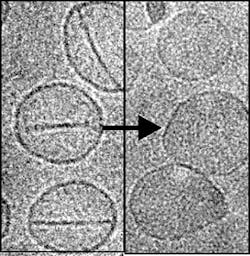

Recognizing that chemotherapeutic drugs often interact with healthy bodily systems such as blood and bone marrow and therefore decrease their effectiveness, researchers at the University at Buffalo (UB) in New York are developing a better drug delivery method by encapsulating the drugs in nanoballoons—tiny modified liposomes that, upon being struck by a red laser, pop open and deliver concentrated doses of medicine. The work could help to improve cancer treatment, reduce its side effects, and boost research about the disease.

In laboratory experiments performed with mice, the researchers hit the nanoballoon with a red laser at the target site in the body. The laser triggered the nanoballoons to pop open and release the drugs. As soon as the laser is turned off, the nanoballoons close, taking in proteins and molecules that might induce cancer growth. Doctors could then be able to retrieve the nanoballoons by drawing blood or taking a biopsy--so the nanotechnology could provide a “chemical snapshot” of the tumor’s environment, which otherwise is very difficult to assess.